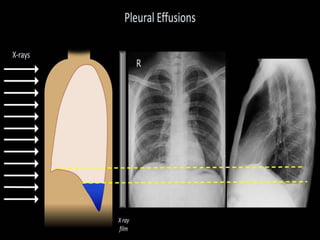

Definitions

• Pleural effusion- excessive accumulation of

fluid in the pleural space

1. Unilateral or bilateral

Types of Pleural effusion

1. Transudative pleural effusions - is caused

by fluid leaking into the pleural space.

2. Exudative pleural effusion - is caused by

blocked blood vessels or lymph vessels,

inflammation, lung injury, and tumors

Investigations

• Chest X-ray

• Ct scan

• Ultrasonography

• Fluid analysis

• Pleural aspiration